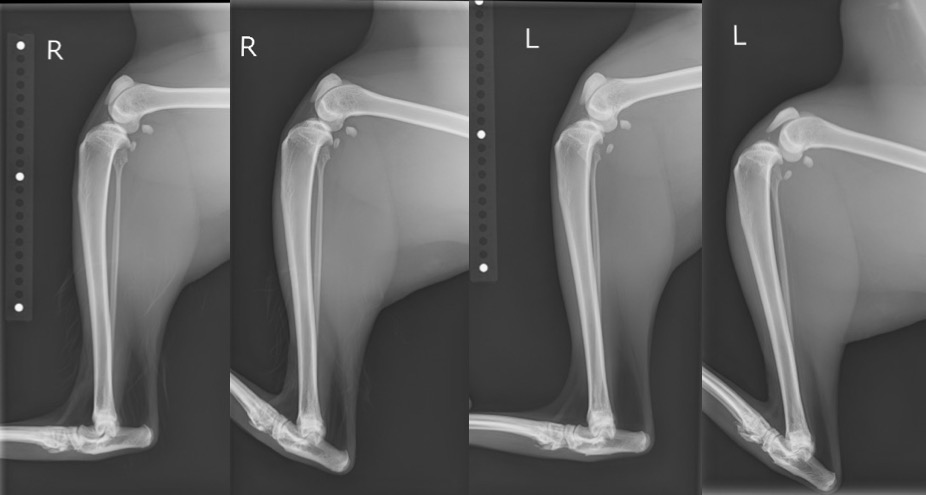

続いて単純X線画像検査を実施したところ、ラテラル像より左側の膝関節にて関節包の腫脹による膝蓋下脂肪体の圧迫(Fat Pad Sign)が認められ、足根関節の過屈曲時撮影像において明らかなCrTTが認められました。

単純X線検査画像(左側では足根関節過屈曲時に明らかなCrTTが認められます。)